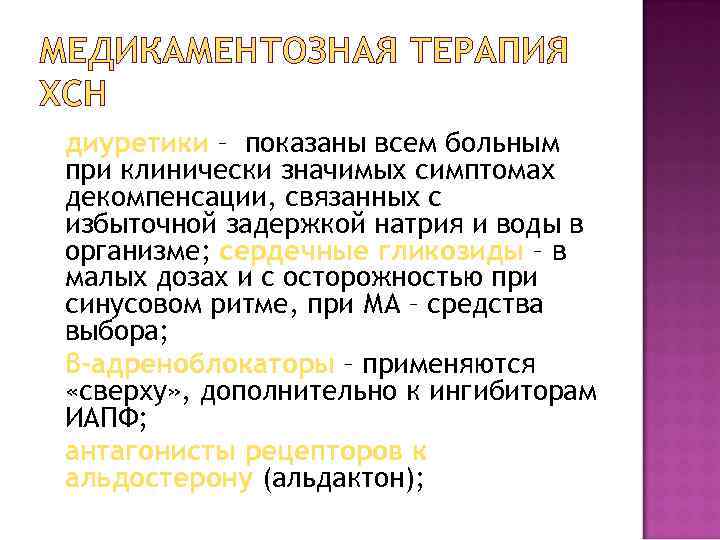

МЕДИКАМЕНТОЗНАЯ ТЕРАПИЯ ХСН диуретики – показаны всем больным при клинически значимых симптомах декомпенсации, связанных с избыточной задержкой натрия и воды в организме; сердечные гликозиды – в малых дозах и с осторожностью при синусовом ритме, при МА – средства выбора; β-адреноблокаторы – применяются «сверху» , дополнительно к ингибиторам ИАПФ; антагонисты рецепторов к альдостерону (альдактон);

МЕДИКАМЕНТОЗНАЯ ТЕРАПИЯ ХСН диуретики – показаны всем больным при клинически значимых симптомах декомпенсации, связанных с избыточной задержкой натрия и воды в организме; сердечные гликозиды – в малых дозах и с осторожностью при синусовом ритме, при МА – средства выбора; β-адреноблокаторы – применяются «сверху» , дополнительно к ингибиторам ИАПФ; антагонисты рецепторов к альдостерону (альдактон);